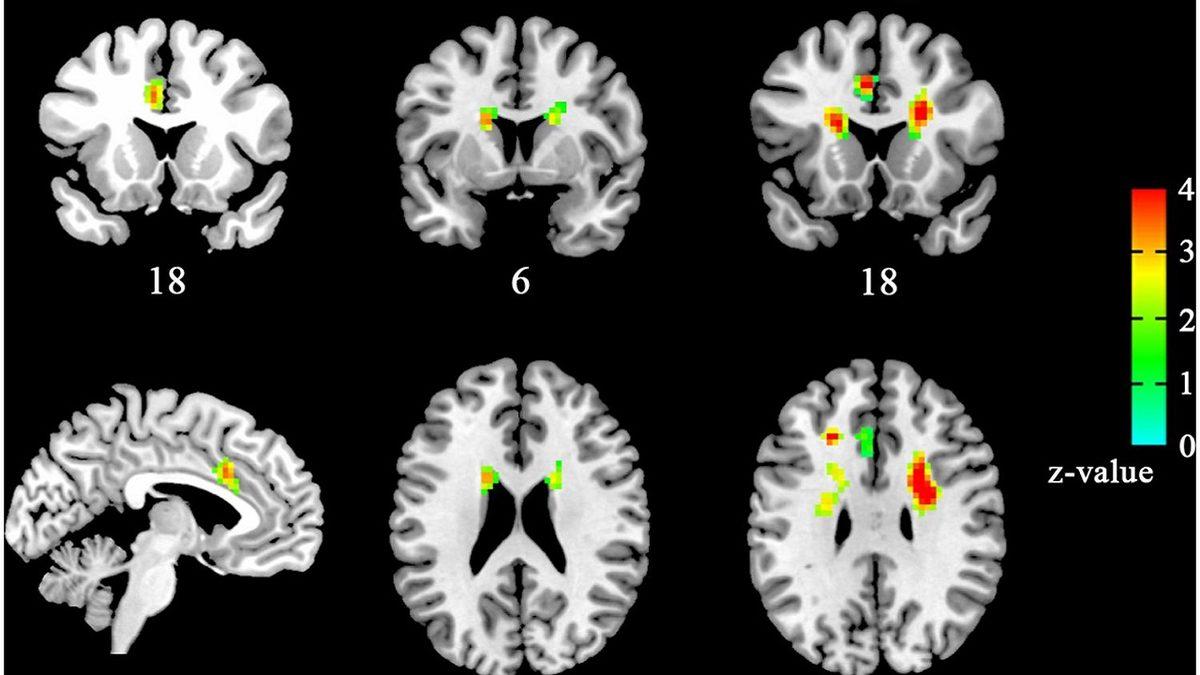

Pek çok davranışbilimciye ve psikoloğa göre de aşkın ne olduğunu ya da aşık olup olmadığımızı anlamanın tek ve basit bir yolu bulunmuyor. Ancak hepsi, bu sorulara cevap verebilmek için aynı yere işaret ediyor; beyin.

Missouri Üniversitesi'nde davranışsal sinirbilimci olan Dr. Sandra Langeslag'a göre bilim insanları aşkın pek çok türünün olduğu konusunda hemfikir ve neler olup bittiğini anlamak için öncelikli olarak hepsi beyne bakıyor. Çevresel etkilerin ve koşulların rol oynayıp durumu değiştirme gücünün olduğu kabul edilse de iş her zaman beyinde bitiyor.